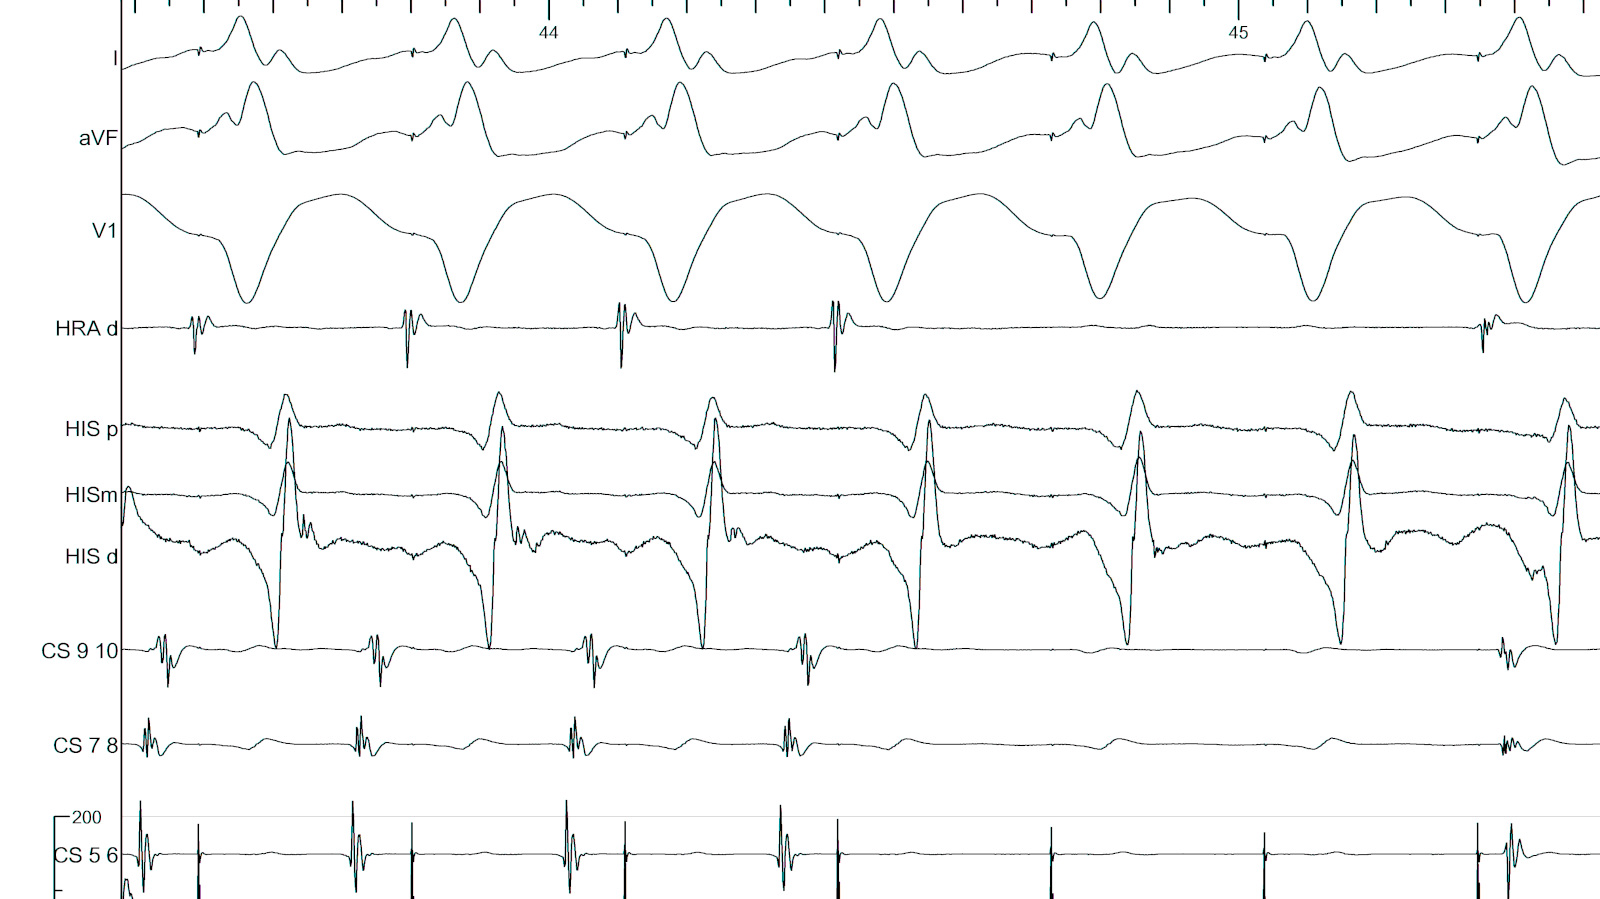

Map and ablate during tachycardia

asap_ablation_tachy.jpg